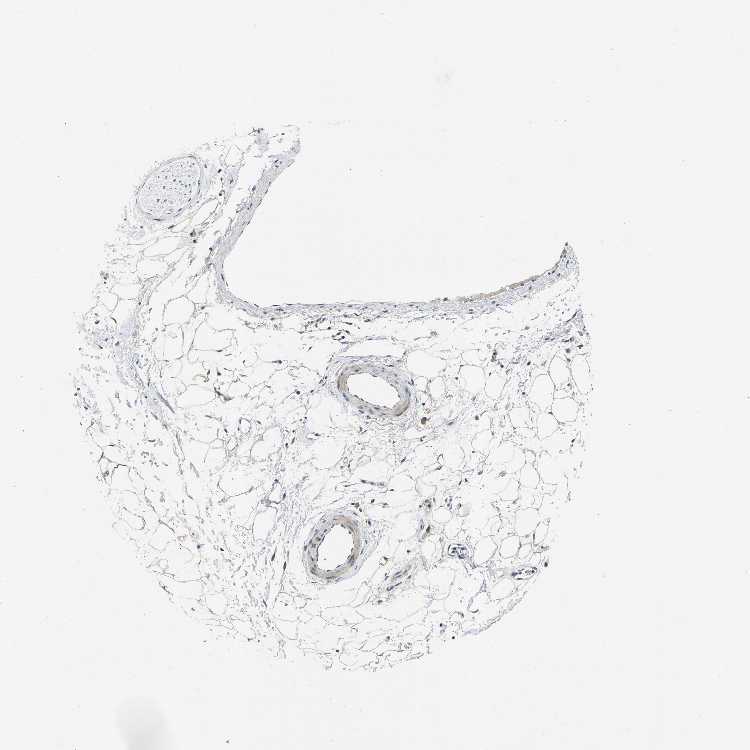

ADIPOSE TISSUE - Antibody stainingi

Antibody staining in the annotated cell types in the current human tissue is reported as not detected, low, medium, or high, based on conventional immunohistochemistry profiling in selected tissues. This score is based on the combination of the staining intensity and fraction of stained cells.

Each image is clickable and will lead to virtual microscopy that enables deeper exploration of all samples and also displays staining intensity scores, fraction scores and subcellular localization as well as patient and tissue information for each sample.

Antibody HPA015242Antibody HPA015968

Adipocytes Not detectedLow